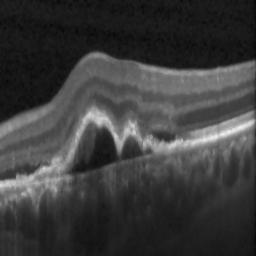

The qualitative results of the proposed system is shown in the Fig. 3. The detection task is evaluated using Area Under the Curve(AUC) metric and the segmentation task is evaluated using Dice Coefficient(DC) metric and the results are presented in Table1

| (a) De-noised OCT slice | (b)Predicted fluid region | (c)Manual fluid segmentation |

|

|

|

| (d) De-noised OCT slice | (e)Predicted fluid region | (f)Manual fluid segmentation |